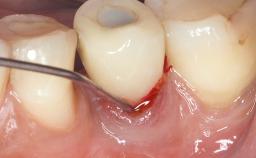

Due to their promising clinical performance, zirconia implants have recently become popular alternatives to titanium implants, particularly for areas with high esthetic demands (Holländer and coworkers 2016; Roehling and coworkers 2016; Lorenz and coworkers 2019). However, regardless of the reported high survival and success rates, zirconia implants were affected by peri-implant diseases over the short observation period, suggesting the importance of treating peri-implant diseases at zirconia implants (Becker and coworkers 2017). In their case, Frank Schwarz and Ausra Ramanauskaite present 3-year results following mechanical debridement alongside Er:YAG laser monotherapy.